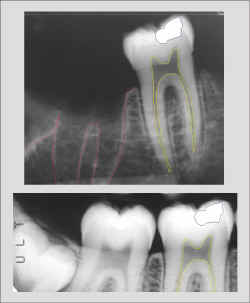

espaco2.gif (821 bytes)Radiografia do suspeito obtida intra-vitae e encaminhada ao IML pelo Cirurgião Dentista que cumpriu seu papel arquivando os exames complementares no prontuário odontológico.

espaco2.gif (821 bytes)Identificação positiva pela comparação computadorizada. Uma única radiografia intra-vitae como a comparada ao lado é suficiente para esta afirmação.

espaco2.gif (821 bytes)Entretando, o processo de identificação prossegue com a radiografia contralateral.